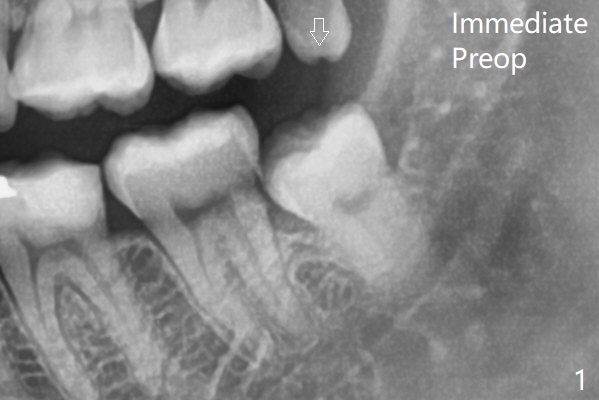

The tooth is out following sectioning twice with the socket inserted with Osteogen plug (Fig.2).